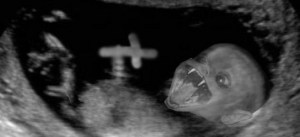

“At 17 weeks, you’ve got a nice little nose and little fingers and hands and the heart’s beating,” he said on Fox News. “It can respond to environmental stimulus. How can you believe that that’s just an irrelevant mass of cells? That’s what they want you to believe, when in fact it is a human being.”

However, according to Dr. Jen Gunter, an OB-GYN and pain medicine physician, the Republican presidential candidate published a study with three other colleagues in 1992 that described using “human choroid plexus ependyma and nasal mucosa from two fetuses aborted in the ninth and 17th week of gestation.”